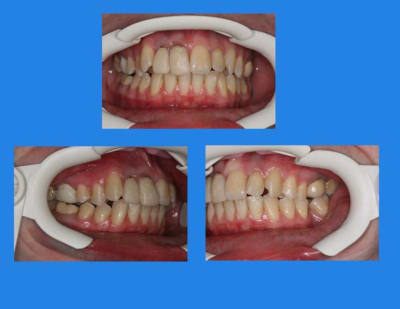

résultat d’élastiques de Cl.II.,

(à ce propos, les arc d’ORMCO, sont très bien et pas cher)

Voici le cas il y a un an

Elle était enceinte de 8 mois,